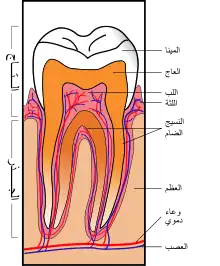

مكونات السن

- يتكون السن من جزء بارز يدعى بالتاج وجزء مغمور داخل عظم الفك يدعى بالجذر.

- تسمى الطبقة الخارجية لتيجان الأسنان بالميناء والطبقة الخارجية المغطية للجذور تدعى بالملاط السني cementum.

- الطبقة الوسطى تسمى بالعاج dentine.

- أما الطبقة الداخلية : فهي اللب السني tooth pulp.

- الميناء السنية أصلب مادة في جسم الإنسان، إذ تشكل المركبات المعدنية حوالي 96% من تركيبها والباقي هو عبارة عن بعض المواد العضوية والماء ويعتبر هيدروكسي الاباتيت Hydroxylapatite المكون الأساسي للميناء السنية وله الصيغة الكيميائية : (Ca5(PO4)3(OH.

- يشكل العاج كتلة السن الأساسية، ويمتاز العاج بلونه البني المصفر، وهو حساس، بمعنى أن انكشافه على الوسط الفموي قد يسبب أعراضا مؤلمة تتفاوت في شدتها حسب طبيعة المنبة وشدته.

- اللب السني، أو الشبكة الوعائية: يوجد اللب السني داخل ما يسمى بالحجرة اللبية pulp chamber وتدخل الأوعية الدموية والألياف العصبية من فتحة ذروة الجذرroot foramen وتصل إلى هذه الحجرة عبر أقنية جذور الأسنان وتسمى بالأقنية الجذرية root canals.

- يُسمّى خط التقاء الميناء مع الملاط السني بخط الالتقاء الملاطي المينائي cementoenamel junction.

- توجد على أطراف الحجرة اللبية خلايا تسمى الخلايا المولدة للعاج odontoblasts، هذه الخلايا تمتلك استطالات خلوية تدعى قنوات tubules توصل الإحساس بالحرارة وبالبرودة وغيرها من المثيرات الحسية إلى النهايات العصبية، تمتد القنوات المذكورة قرب خط الالتقاء المينائي العاجي Amelo-dentino junction.

- يشكل الملاط السني غلافا حول جذر السن يربط السن بالعظم السنخي المحيط به، إذ تغمد فيه ألياف ضامة تدعى بألياف شاربي قادمة من العظم المحيط. يسند الرابط حول السني مهمة ربط السن بالعظم المحيط ارتباطاً مرنا يمكنه من تخميد الجهود الإطباقية الناجمة عن الفعالية المضغية للسن.[2]